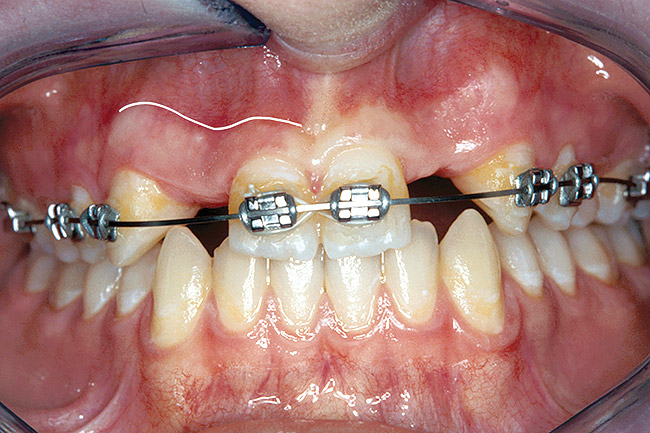

Before the day of surgery, the patient was seen by the orthodontist for the removal of the orthodontic brackets. The patient still was not pleased with the position of the two centrals, and it was determined that this would be addressed after implant placement (Figure 26). The anatomical variations of the crestal tissue and lack of interdental papilla can be appreciated in the close-up views of the right and left sites (Figure 27 and Figure 28). There were no surprises on the day of surgery as all of the decisions were made during the planning phase, before the scalpel ever touched the patient. The occlusal view of the CT 3D model revealed the wider alveolar ridge on the right side and thinner crest on the left side (Figure 29). This was confirmed when the full-thickness mucoperiosteal flaps were elevated, and the underlying bone revealed (Figure 30). The tooth-borne templates were designed to facilitate the drills and drilling sequence specific to the diameters of the predetermined implants (Figure 31). Each template contained an embedded 5-mm long stainless steel tube, which was approximately 0.2-mm wider than each drill (just wide enough to allow for the drills to rotate freely). Once positioned over the natural teeth, the template was secure and offered precision accuracy in transferring the implant locations from the original software-designed plan, allowing the potential for internal and external irrigation (Figure 32).

Figure 26  VIRTUAL PLANNING AND SURGERY Before implant surgery, the orthodontic brackets were removed, revealing the position of the centrals, and the anatomical variations of the crestal tissue and lack of interdental papilla.

Figure 26

Figure 27   VIRTUAL PLANNING AND SURGERY Before implant surgery, the orthodontic brackets were removed, revealing the position of the centrals, and the anatomical variations of the crestal tissue and lack of interdental papilla.

Figure 27

Figure 28   VIRTUAL PLANNING AND SURGERY Before implant surgery, the orthodontic brackets were removed, revealing the position of the centrals, and the anatomical variations of the crestal tissue and lack of interdental papilla.

Figure 28